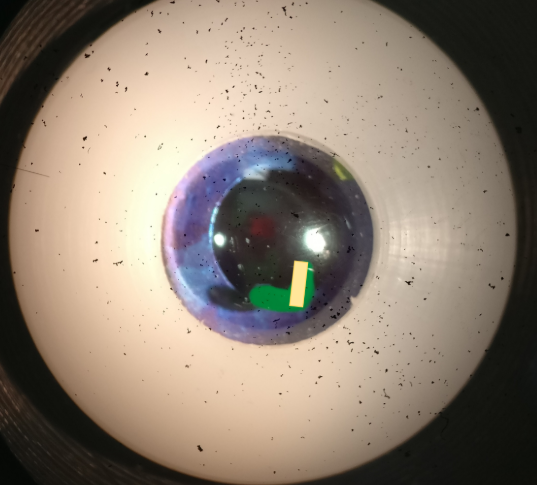

what slit lamp technique is being demonstrated on the model eye in this image

optic section

what slit lamp technique is being demonstrated on model eye in this image

parallelpiped